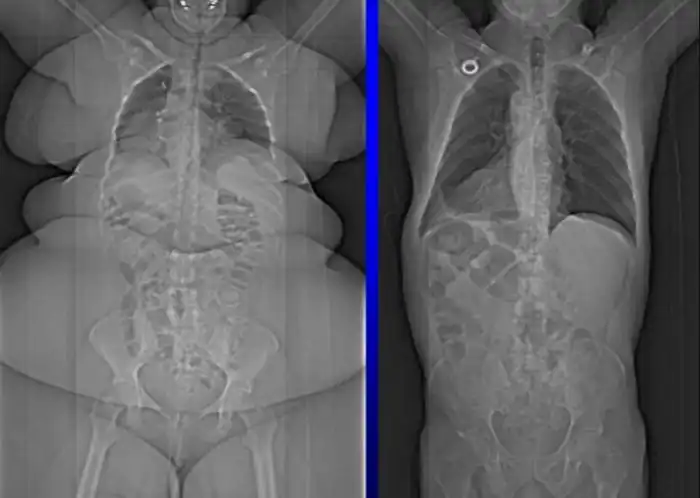

7. Сравнение рентгеновских снимков полного человека и худого